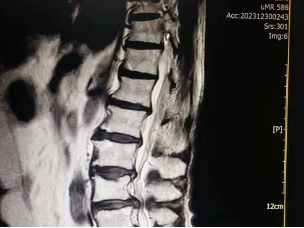

腰椎间盘突出症MRI

腰椎间盘变性的过程(磁共振示图:正常和退变)

正常的椎间盘:MRI T2加权高信号(图1、2);退变的椎间盘:MRI T2加权低信号(图3、4、5)。